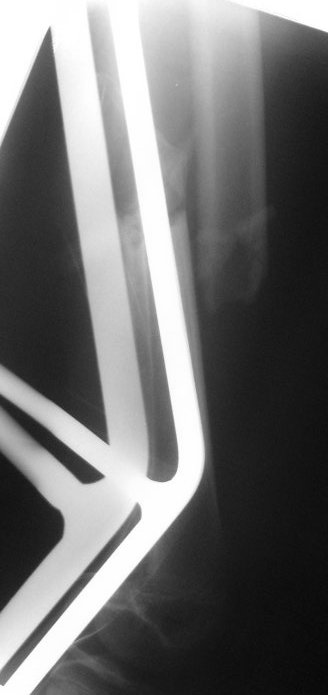

На сегодняшний день вот такая картина: девочка, 13 лет, 3 недели на скелетном вытяжении по поводу оскольчатого перелома нижней трети левого бедра.

Сейчас инфекцию "победили", отек бедра за последние дни значительно спал, но имеется укорочение 2 см, отломки уже "прихватились",

патологической подвижности нет.

Имя     : femur_AP.jpg